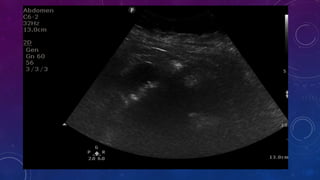

MULTIPLE GALL STONES

GB AND RIGHT RENAL CALCULI.